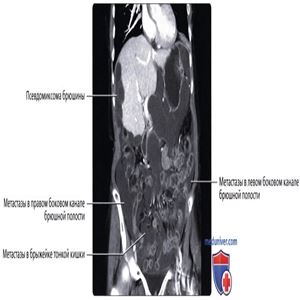

КТ с контрастированием, аксиальный срез: классическая картина псевдомиксомы брюшины: метастатическое поражение брюшины муцин-продуцирующей опухолью червеобразного отростка приводит к формированию скопления желатинообразного вещества в брюшинной полости. Формирование капсул и количество вещества обусловливают характерный масс-эффект, или вдавления, на внутренние органы полости живота и часто вызывают обструкцию кишечника.

КТ с контрастированием, аксиальный срез: у этого же пациента определяется сложный (с наличием перегородок) характер «асцитической жидкости», часто являющейся полужидким желатинообразным веществом. Метастазы наблюдаются по всей полости брюшины, включая метастазы, расположенные по поверхности печени, сальника и боковых каналов брюшной полости. Обратите внимание, что почки не подвержены влиянию опухоли благодаря своему забрюшинному положению.

КТ с контрастированием, объемный рендеринг, корональный срез: у пациента с миксомой брюшины определяются классические «вдавления» на поверхности печени, обусловленные муцинозными вставками и распространенным метастатическим поражением всей брюшинной полости.